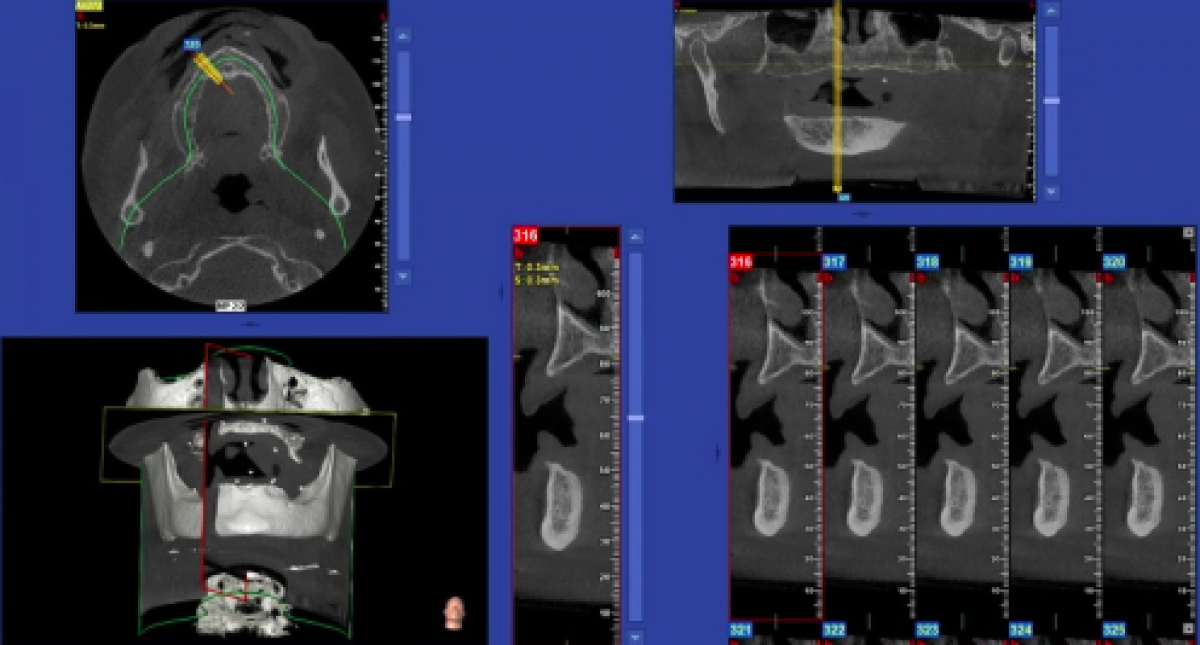

Let us consider a case of complete edentulism in a very young patient, but without teeth for more than 20 years. This treatment is to be finalized via 8 implants, positioned with a software-assisted surgical guide using a non-flapless approach.

The Cone Beam 3D exam was acquired using the NewTom GiANO HR Professional and a 13 x 10 cm FOV (Field Of View, or volume size).

The great leap occurs mentally in the moment we are able to "look at" the patient, already imagining him/her in 3D. That is, imagining the effects of centripetal resorption of the upper jaw, the reduction of volumetric size referred to the correct spatial planes (coronal-apical in fig. 6-8 and bucco-palatal in fig. 9), yet with the awareness that we are unable to imagine the density of the medullary component, which will strongly impact the scope for immediate implantation.